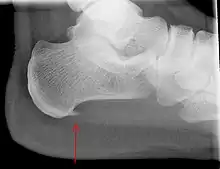

An incidental finding associated with this condition is a heel spur, a small bony calcification on the calcaneus (heel bone), which can be found in up to 50% of those with plantar fasciitis.[6] In such cases, it is the underlying plantar fasciitis that produces the heel pain, and not the spur itself.[13] The condition is responsible for the creation of the spur though the clinical significance of heel spurs in plantar fasciitis remains unclear.[12]

Medical imaging is not routinely needed. It is expensive and does not typically change how plantar fasciitis is managed.[15] When the diagnosis is not clinically apparent, lateral view X-rays of the ankle are the recommended imaging modality to assess for other causes of heel pain, such as stress fractures or bone spur development.[7]

The plantar fascia has three fascicles-the central fascicle being the thickest at 4 mm, the lateral fascicle at 2 mm, and the medial less than a millimeter thick.[19] In theory, plantar fasciitis becomes more likely as the plantar fascia's thickness at the calcaneal insertion increases. A thickness of more than 4.5 mm ultrasound and 4 mm on MRI are useful for diagnosis.[20] Other imaging findings, such as thickening of the plantar aponeurosis, are nonspecific and have limited usefulness in diagnosing plantar fasciitis.[13]